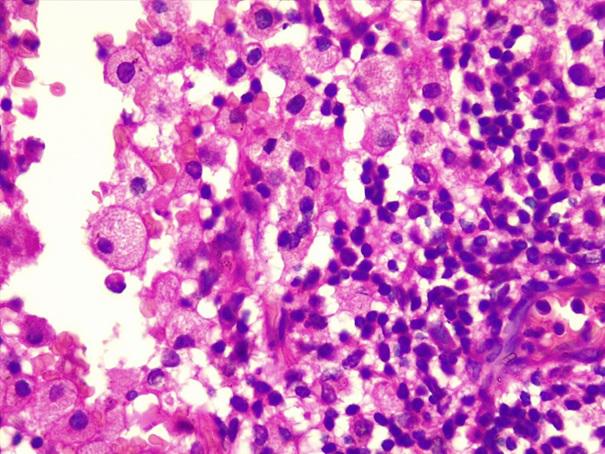

*Case 2 : Dr Rimamskep Ifusumu/ Prof Modupeola Samaila

email: mamak97@yahoo.com

Clinical details: Female, 38years, Ovarian mass ?